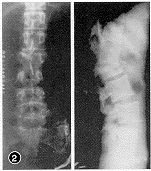

本组23例术后随访最短24个月,最长5年4个月,平均3年8个月。术前脊柱后凸畸形,后凸角18°~45°,平均27.5°,术后为0°~16°,平均6°。17例新鲜骨折病人术后基本矫正(图2~5,插Ⅱ),6例陈旧骨折术后仍有轻度畸形。术后每月摄片1次,骨愈后时间为5~8个月,平均为6个月。术后2例病人出现气胸,均经胸腔闭式引流1周后痊愈。23例病人术前均有不同程度的截瘫,除1例D级为伤后4年,因后凸角较大,故术中做前路植骨,以重建其脊柱中柱、前柱,矫正其后凸成角为目的外,22例均有Frankel一级以上的改善。13例术前有括约肌功能障碍者术后随诊时大部或完全恢复。

图2 X线示L1爆裂骨折 图3 CT扫描示L1前、中、后柱损伤,椎管2/3梗阻 图4 术后随诊X线像示椎体前缘恢复正常高度,椎间隙有骨小梁通过 图5 术后CT扫描示椎管内骨块彻底清除,植骨块与档板位置适中